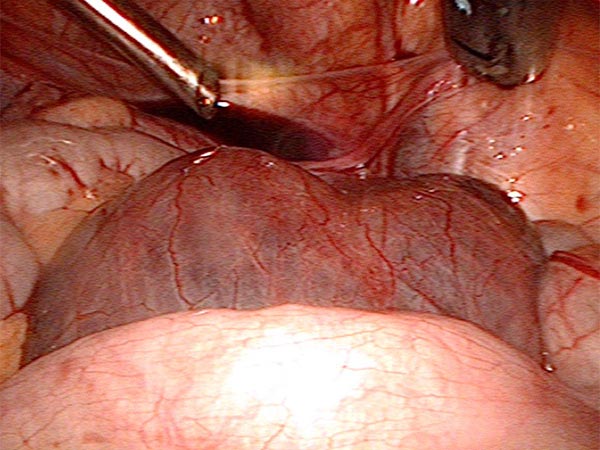

Laparoskopische Resektion: Blick vom Nabel zum Unterbauch mit etwas freier Flüssigkeit auf der Blase, davor wölbt sich eine große retroperitoneale Zyste (LM) vor.

Blick zum rechten Unterbauch, die Fasszange zeigt auf eine Zyste vor dem Coecum und der Appendix.